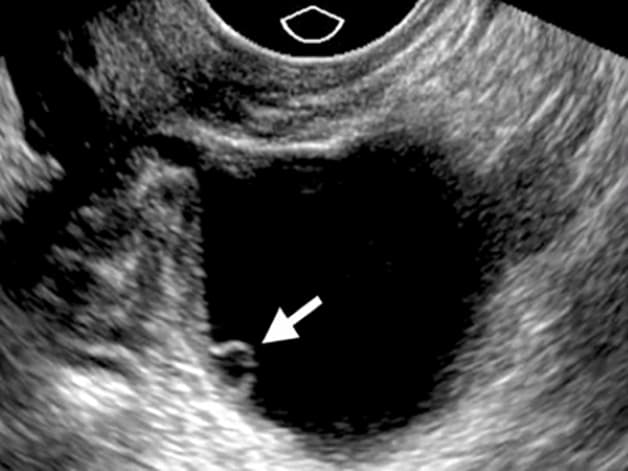

Siêu âm trứng hay còn được gọi là siêu âm canh trứng, đây là một phương pháp kỹ thuật có vai trò lớn trong hỗ trợ sinh sản. Quá trình thực hiện phương pháp này sẽ theo dõi sự phát triển của trứng (nang noãn) bằng đầu dò âm đạo trong 1 chu kỳ với mục đích tăng khả năng có con theo ý muốn cao nhất. Không chỉ nắm giữ vai trò theo dõi sự phát triển của nang noãn mà siêu âm trứng còn có giúp chị em dự đoán được ngày rụng trứng, từ đó có thể chủ động thực hiện những biện pháp để mang thai.

Siêu âm trứng để kiếm tra sự phát triển của nang noãn là một trong những bước đầu cần phải thực hiện khi thăm khám vô sinh, hiếm muộn. Bác sĩ có thể chỉ định siêu âm đầu dò hoặc siêu âm ổ bụng để kiểm tra được sự phát triển của nang noãn. Kết hợp cùng với những dấu hiệu lâm sàng, bác sĩ sẽ yêu cầu bạn thực hiện siêu âm để đánh giá chất lượng của buồng trứng khi điều trị vô sinh. Siêu âm trứng giá bao nhiêu cũng sẽ phụ thuộc vào tình trạng mức độ bệnh hiện tại năng hay nhẹ và có thực hiện thêm bất kỳ xét nghiệm nào nữa hay không.

Đối với những người bình thường, đầu chu kỳ nang trứng chỉ nhỏ tầm khoảng 4 -5mm chưa nhìn thấy được thông qua hình ảnh siêu âm. Vào ngày thứ 7, ngày thứ 8 của chu kỳ kinh, khi siêu âm bác sĩ có thể thấy nang trứng phát triển kích thước khoảng 10-12mm. Trung bình mỗi ngày đối với nang trội sẽ phát triển 1-2mm.

Đến giữa kỳ kinh nguyệt, một nang trứng đủ lớn để rụng, chỉ có một hoặc hai nang trứng trong chu kỳ trưởng thành để rụng. Vào trong khoảng ngày thứ 14 của chu kỳ kinh nguyệt, nang trứng đạt tới kích thước từ 17-18mm sẽ gọi là nang trứng trưởng thành và chuẩn bị rụng xuống hay còn gọi là phóng noãn.

Thông thường, với các mẹ chậm có con thường được siêu âm ngày thứ 2 của chu kỳ để bác sĩ tiến hành đếm số lượng nang noãn thứ cấp và để chẩn đoán tình trạng bệnh. Còn đối với trường hợp bệnh nhân siêu âm nang noãn thông thường là để xác định ngày thụ thai tốt nhất. Việc siêu âm trứng thường bắt đầu từ ngày thứ 7 của chu kỳ đối với người có chu kỳ kinh nguyệt 28 ngày và sẽ được hẹn siêu âm lại. Kích thước nang noãn đạt khoảng từ 20-28mm, trứng rụng sẽ đạt được chất lượng tốt nhất.